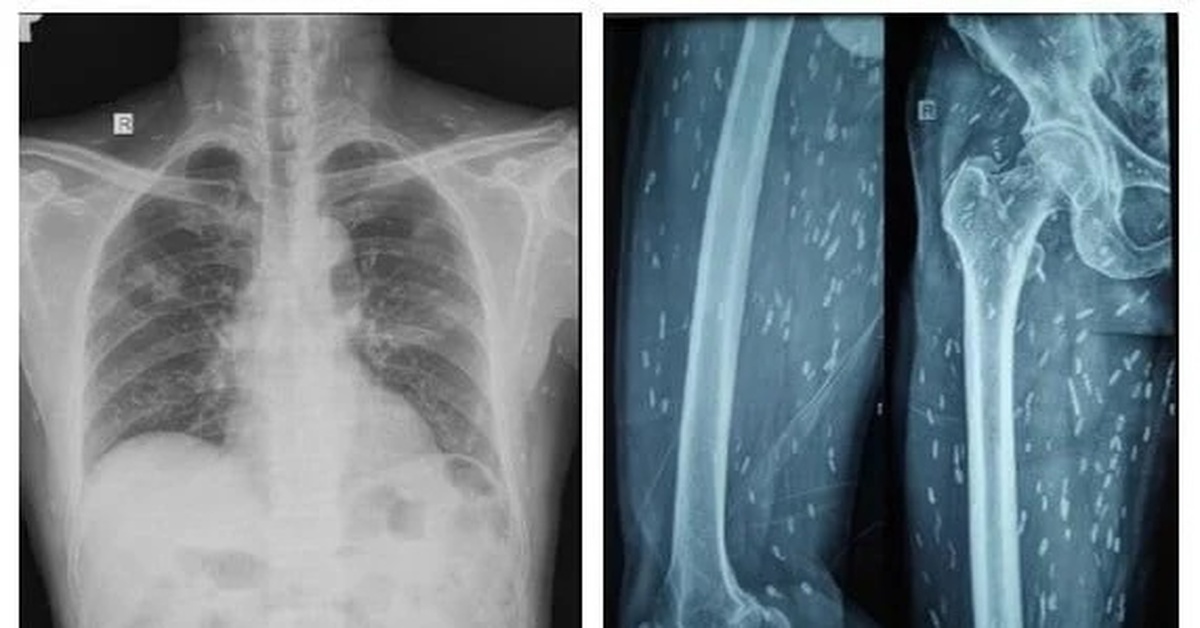

9 người nhập viện do uống rượu được điều trị tại Bệnh viện Đa khoa Hùng Vương - Ảnh: BVCC